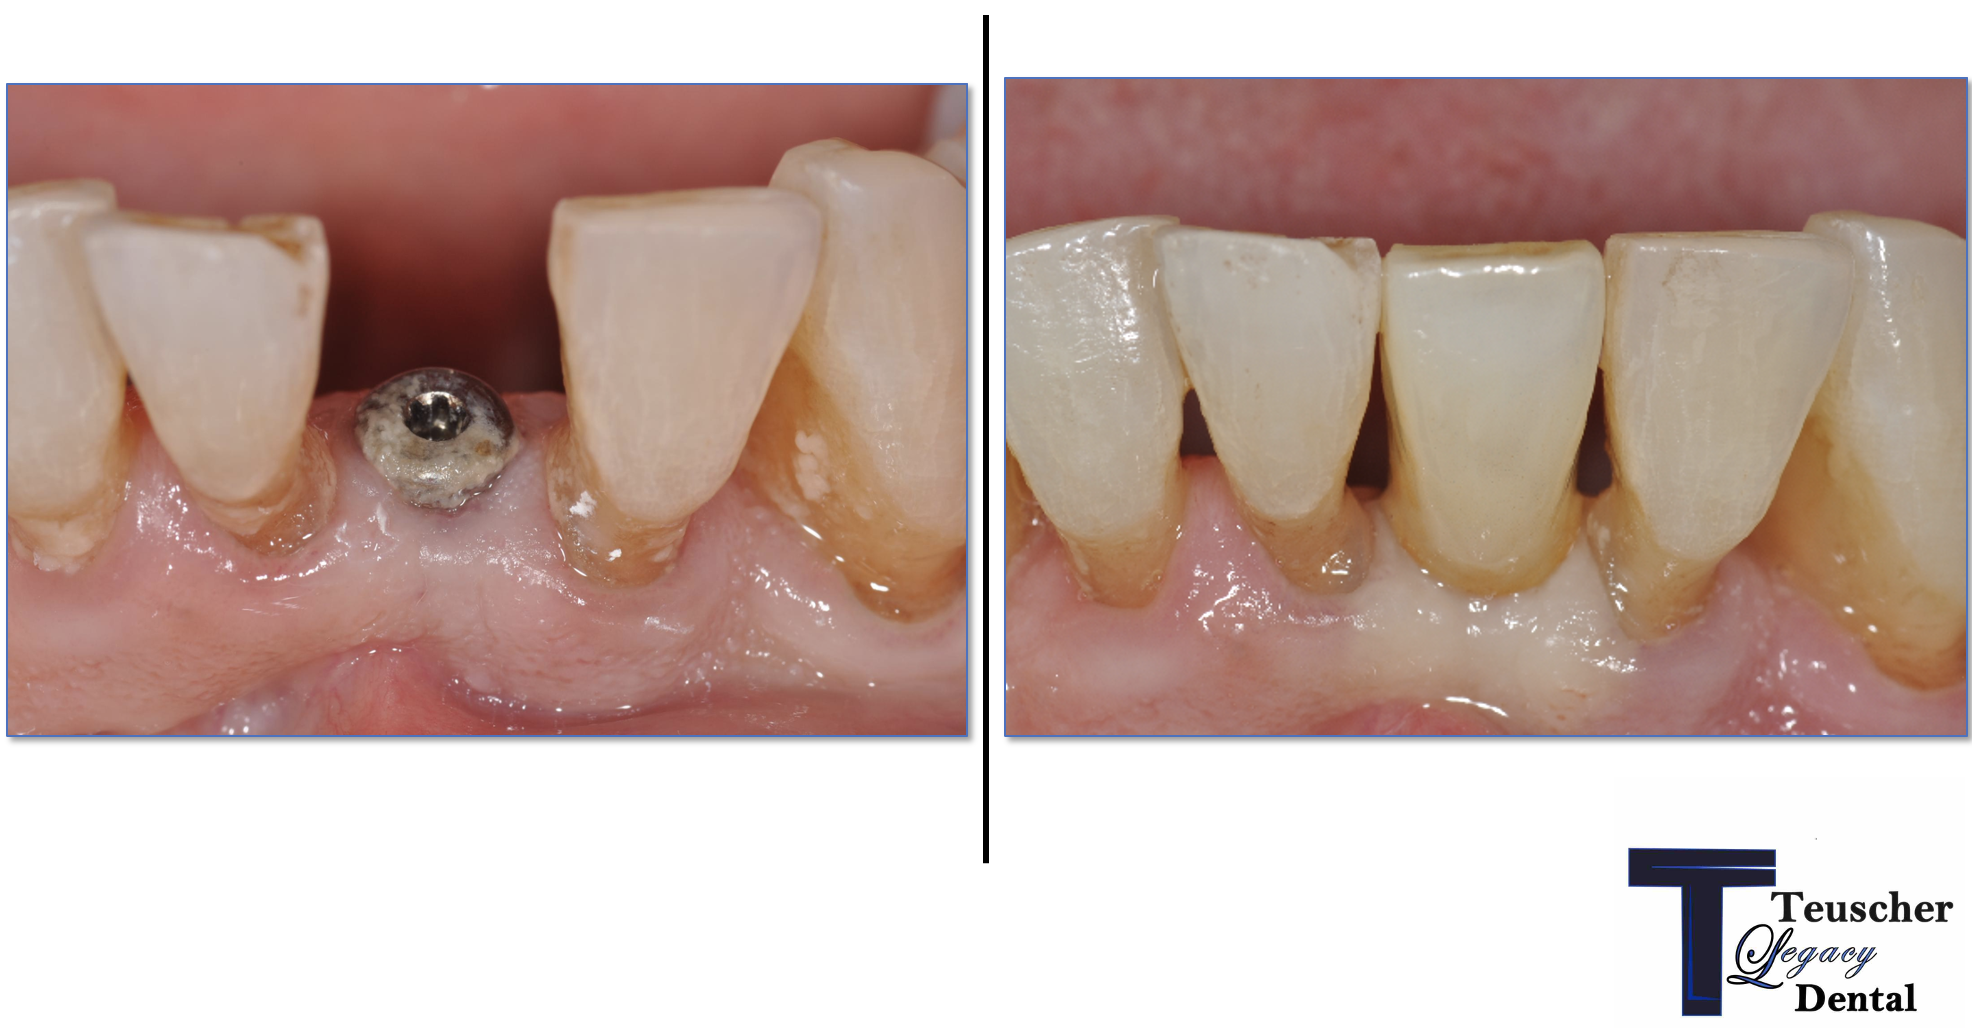

How We Restored a Front Tooth with a Dental Implant — Start to Finish

They’re what people notice first. So when a front tooth is missing or damaged — whether from trauma, decay, or failed restorations — it’s not just about replacing it. It’s about doing it perfectly in the smile.

In this case study, we’ll walk you through one of the more complicated — and rewarding — procedures we do at our practice: a front tooth dental implant. You’ll see how much thought, planning, and precision goes into restoring one small tooth… and why every step in the dental implant process matters.

Once everything is stable, we place the final custom crown. Shade, translucency, shape, and surface texture are all matched to your natural teeth so the implant blends in seamlessly.